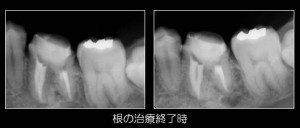

その辺を気をつけながら、神経管の中の細菌感染を除去していくと・・・

案の定予想通り神経管の脇のところに神経管とは違う穴が開いていました(パーフォレーションと言います)。この穴が外と交通しているので、常に細菌が出たり入ったりしており、結果として膿の袋を作ってしまっていたのです。

なので、この穴は放置するわけにはいかず、しっかりと洗浄した後、特殊な材料で封鎖をしました。その後、神経管もしっかりキレイに洗浄して最終的な詰め物をしました。